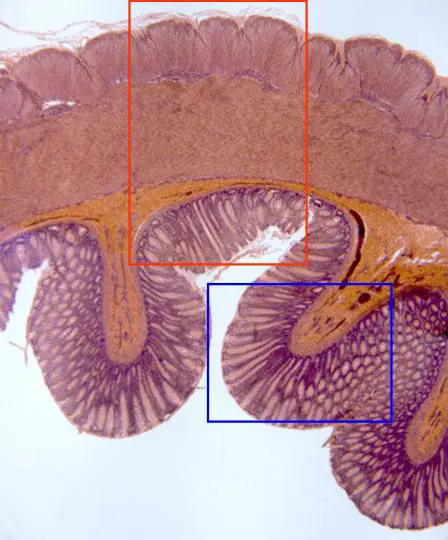

dijo:Aspecto de parte de una sección de intestino grueso, teñida con hematoxilina/eosina y observada con el objetivo de 4x. A este bajo aumento se llegan a distinguir las diferentes capas que integran su pared y que de fuera a dentro son: serosa, muscular, constituida a su vez por una túnica externa y otra interna, submucosa y finalmente mucosa, directamente en contacto con la luz del órgano. En otras microfotografías se muestran detalles a mayores aumentos de cada una de estas zonas (áreas encuadradas en rojo y en azul)

dijo:Reconstrucción fotográfica con el objetivo de 10x de la pared completa del intestino, pudiéndose apreciar con mayor detalle las capas que la forman, de fuera a dentro: serosa, muscular externa e interna, submucosa y mucosa, esta última con numerosas criptas de Lieberkühn, en contacto con la luz intestinal. Entre las dos túnicas musculares se sitúan una serie de ganglios nerviosos, pertenecientes al plexo de Auerbach. En otras microfotografías se muestran detalles a mayor aumento de la serosa y túnicas musculares, así como de la mucosa (zonas encuadradas en rojo, amarillo y azul, respectivamente)

dijo:(Zona encuadrada en rojo) Aspecto de la serosa y parte de la túnica muscular externa del intestino, con el objetivo de 40x. La serosa está formada por un epitelio (mesotelio) y conectivo subyacente, siendo visibles los núcleos de las células epiteliales y conectivas, además de algún vaso sanguíneo. Por debajo se observan las fibras musculares lisas de la túnica externa, cortadas transversalmente, con aparentes núcleos teñidos de azul

dijo:(Zona encuadrada en amarillo) Con el objetivo de 40x se aprecia parte de la túnica muscular interna del intestino, formada por fibras lisas dispuestas circularmente, por lo que aquí aparecen cortadas de forma longitudinal, mostrando cada una en el centro el núcleo teñido de azul por la hematoxilina

dijo:(Zona encuadrada en azul) Detalle, con el objetivo de 100x, del fondo de las criptas de Lieberkühn, distinguiéndose con claridad las células integrantes por sus núcleos teñidos de azul. En la parte superior de la microfotografía se aprecia parte de la capa muscular de la mucosa, formada por fibras lisas, de las cuales también son visibles sus núcleos